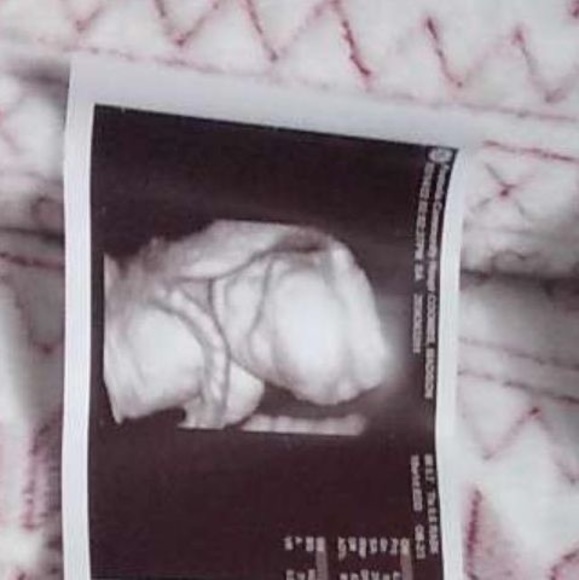

Hello! Congrats on your sweet baby on the way. I hope you received the Doppler and would consider changing your rating now that you have it. I apologize if shipping was delay by USPS as it was in the mail within 48 hrs of your order. Congrats again!

@kmacgregor1 umm if it comes today yes I’ll definitely change it I do appreciate the update on wether it was coming or not thank you